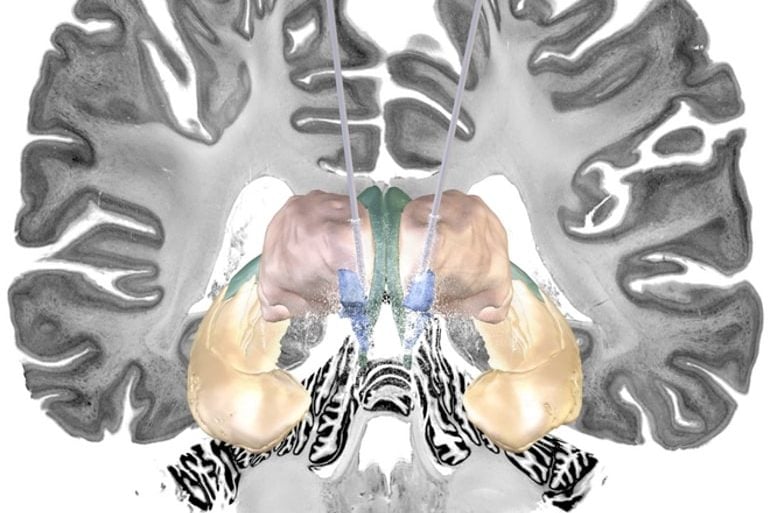

Accountable for the different perception is a particular part of the olfactory brain – the piriform cortex. This brain area is activated before someone senses an odour. The piriform cortex processes what we see und creates an expectation about how a something is going to smell. This expectation influences how we actually experience the smell. The fMRI-data showed that the cells of the piriform cortex got active, before a scent was in the air.

In previous studies, researchers had always presented the pictures and the odours at the same time. “Only now that we analyzed the interaction of olfactory and visual information in a timely separated manner, we were able to see that the piriform cortex is activated before we smell something,” explains Suchan his study. The neuropsychologists plan a future study about the role of the piriform cortex in body perception. “We assume a social component,” says Suchan.

Image Source: NeuroscienceNews.com image is credited to RUB, Marquard.